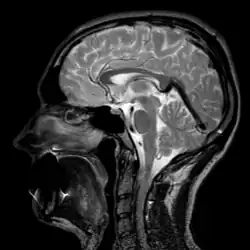

- Магнитно-резонансная томография